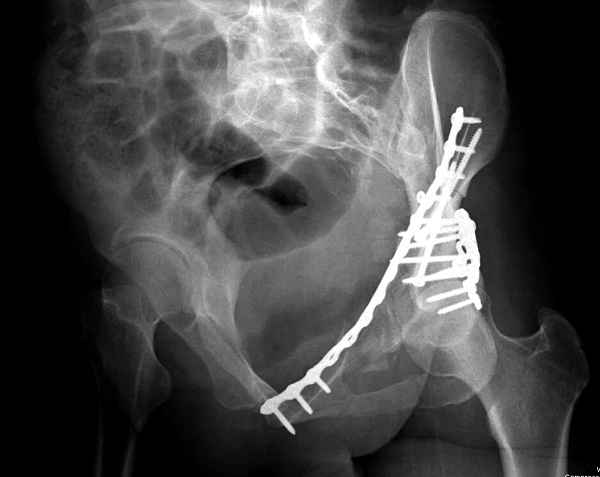

Здесь несколько вариантов двухколонных свежих переломов, которые были оперированы из одного-заднего, а также из двух: переднего и заднего доступов.

Имя     : 3 Both column one incision.jpg

Тип     : image/jpeg

Имя     : 4 Both column one incision.jpg